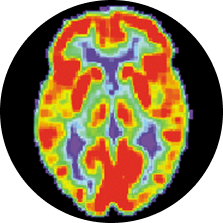

Lit up image of a brain scan

Positron Emission Tomography (PET scans)

Researchers first inject a tracing chemical that binds to the tau proteins in CTE, then use a special brain scanner to trace where the chemical settles in the brain. With a tracer chemical that binds to CTE tau (and only CTE tau), this technique could show us the tell-tale distribution of tau tangles while someone is still alive. Several research groups have developed such a chemical, and early studies in athletes are already underway.